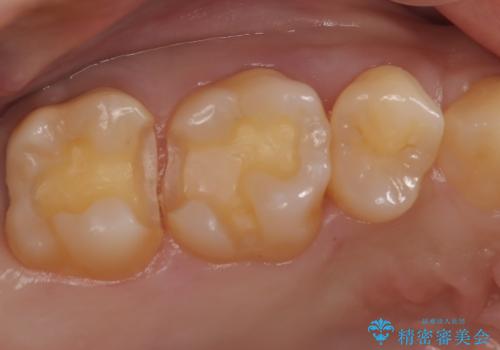

- 金属を外してセラミックを入れたいことを主訴に来院された患者さんです。

セラミックインレーにて修復を行いました。

当院でのセラミックインレーは、ラバーダムを使用して装着しております。